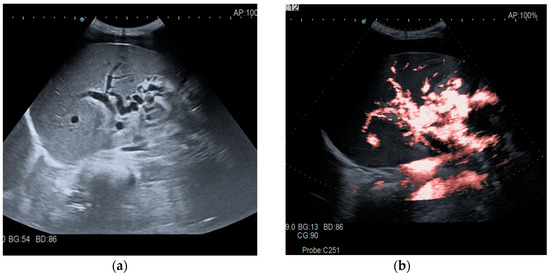

Figure 1.

Portal cavernomatous transformation. (a) Multiple serpiginous echo-free structures (vessels) replacing the normal portal vein are seen in B-mode at the hepatic hilum; (b) Color Doppler examination confirms the presence of venous flow within the vessels of the cavernoma.

Transabdominal ultrasound with Doppler protocol (Figure 1a,b and Figure 2a,b), CT scan (Figure 3a,b), and MRI (Figure 4a,b) were used for the diagnosis in 88.9, 75.1, and 15% of cases, respectively. CEUS was used for the diagnosis in 49 cases (25.9%) but in only 29 cases was it used for the evaluation of the thrombus, and in two cases for cavernoma diagnosis (Figure 5a,b and Figure 6a,b).